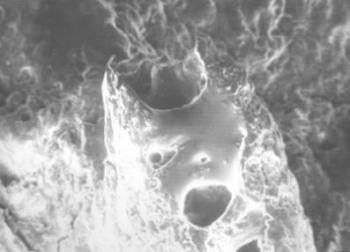

41. ábra. A csontkinövések csúcsán elhelyezkedő pórusokba insertálódtak az ínrostok. SEM 450× nagyítás